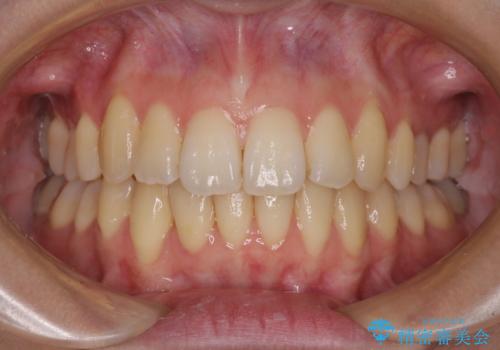

右上第一小臼歯は歯根癒着により移動せず、左上第二小臼歯は移動はするものの非常に動きが鈍かったため、抜歯したスペースを閉じるまでに非常に時間がかかってしまいました。

患者様には辛抱強く治療にお付き合いいただき、すっきりとした口元に仕上げることができました。